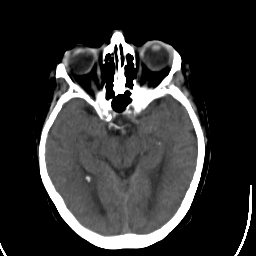

Stroke CT #1 -- Slice #10

[Home][Help][Clinical] Slice 10